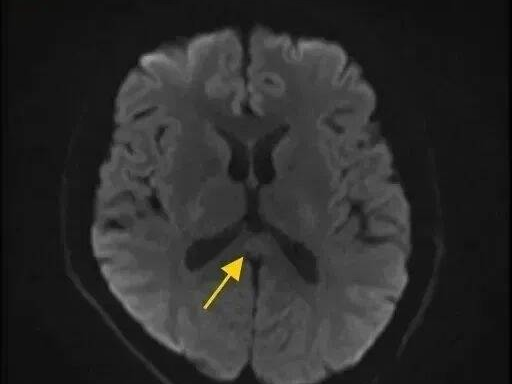

清洁剂各有不同功效,不要以为混合使用效果会更好,严重时可能产生有毒气体,或导致灼伤。

图源:深圳卫健委